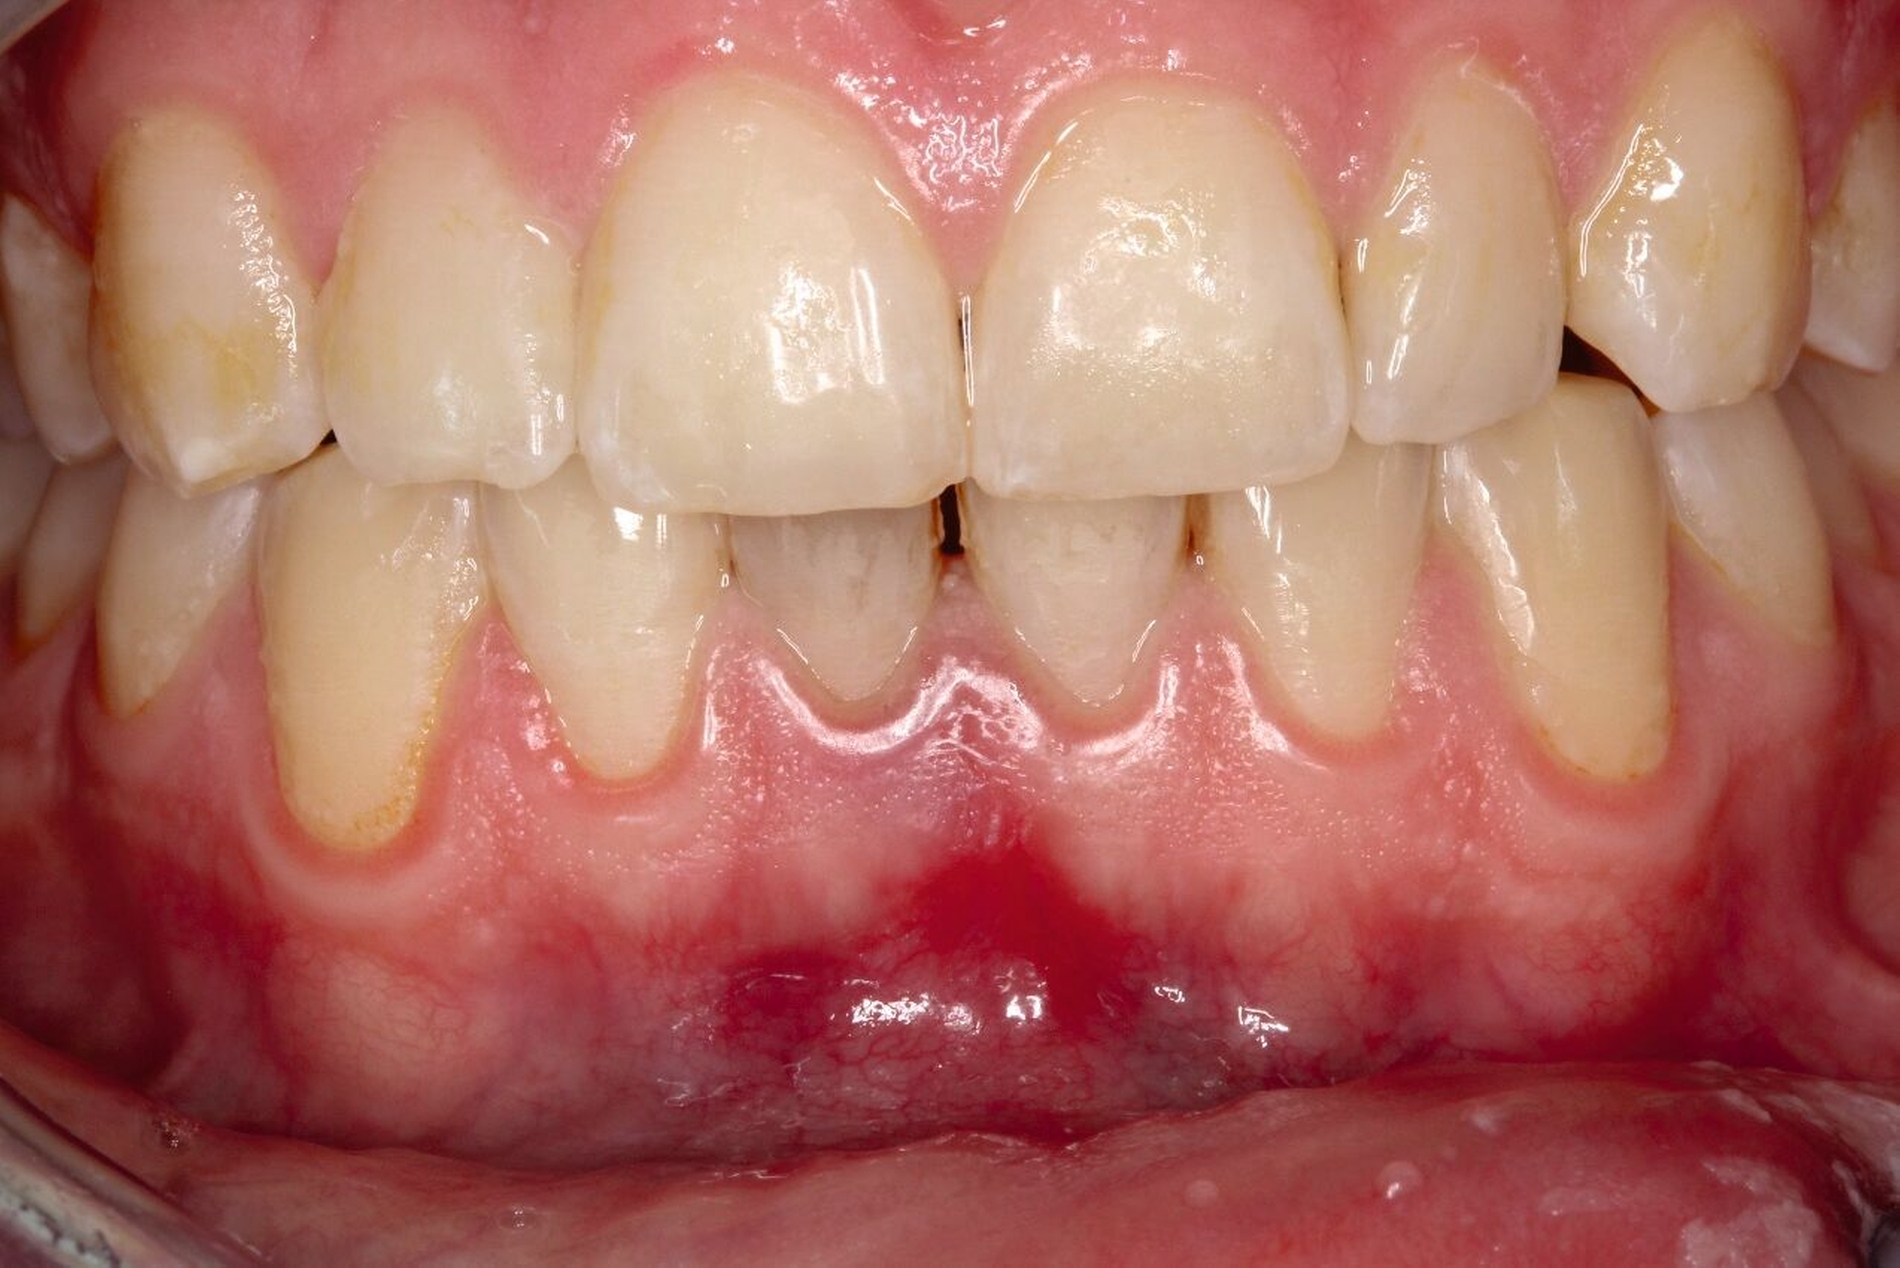

Zusätzlich zeigten sich ein dunkel-bläuliches Hämatom sublingual in Regio 32 bis 42 und ein korrespondierendes Hämatom im Vestibulum zwischen den Zähnen 31 und 41 (Abbildungen 1 und 2). Beide schienen mit der extraoralen Kinnwunde zu korrelieren und waren auf Palpation schmerzhaft. Es konnten keine Stufen ertastet und keine Krepitation wahrgenommen werden (Flowcharts Abbildungen 13 und 14).